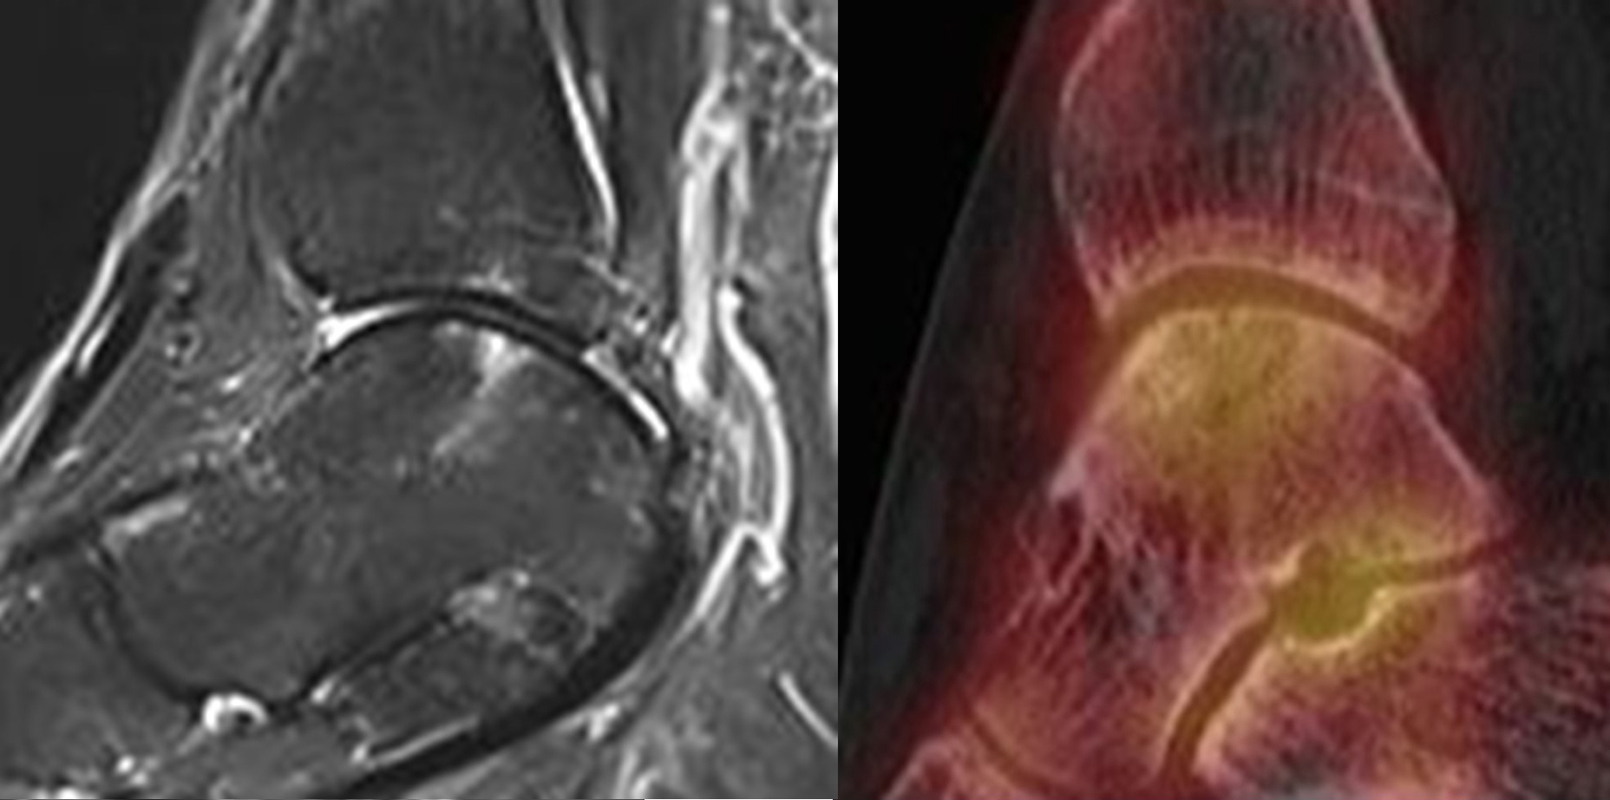

Abbildung 2.1.

Bildbeispiele symptomatische OCL

Zum Lesen der Bildbeschreibung und zur Vollansicht bitte das Bild anklicken. Bild: H. C. Rischke

Abbildung 2.2.

Bilder eines Patienten mit Z. n. mehrfachen Sprunggelenksdistorsionen in der Vergangenheit, besonders heftige Distorsion des linken Sprunggelenkes 5 Wochen vor der Untersuchung. Die SPECT/CT zeigt eine instabile osteochondrale Läsion mit deutlicher Aktivierung.

Abbildung 2.3.

Klärung bei Schmerzen im rechten OSG bei OCL an der medialen Talusschulter. Z. n. OSG-Distorsion vor 2 Jahren und Z. n. OSG-Fraktur / Syndesomosenruptur. Ausgedehnte OCL, hier jedoch kein erhöhter Knochenmetabolismus; lediglich Nachweis einer Stressreaktion im Bereich der Synchondrose eines Os trigonum als Schmerzursache.